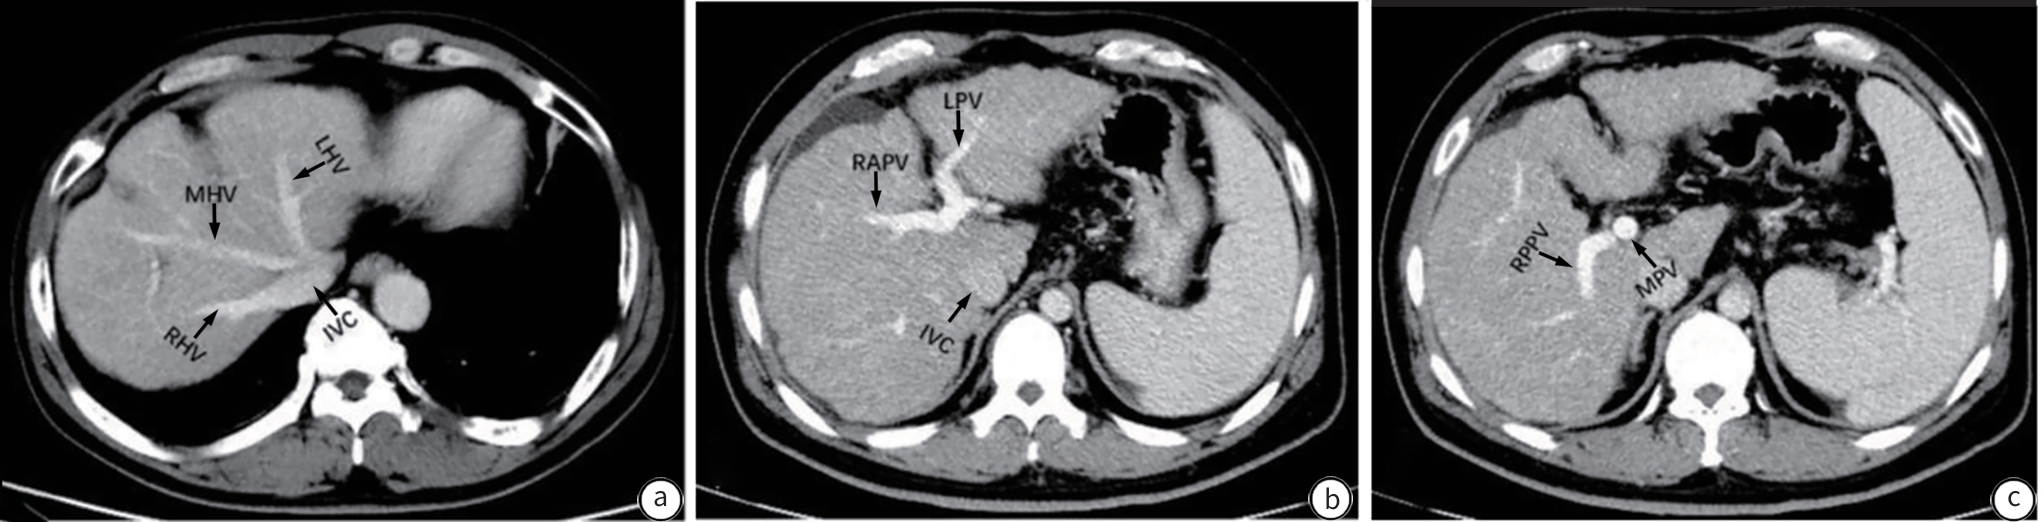

Expert consensus on clinical practice for the diagnosis and treatment of hepatic vascular diseases (2026 edition)

Committee on Liver Diseases (Integrated Traditional Chinese and Western Medicine), China Research Hospital Association, Committee on Interventional Medicine, China Research Hospital Association, Branch for Multidisciplinary Diagnosis and Treatment of Portal Hypertension, Beijing Medical Doctor Association

2026, 42(1): 47-65. DOI: 10.12449/JCH260107

Abstract(1097) HTML (617) PDF (1269KB)(526)

Abstract:

Hepatic vascular diseases (such as portal vein thrombosis, porto-sinusoidal vascular disease, hereditary hemorrhagic telangiectasia, arterioportal fistula, and sinusoidal obstruction syndrome, Budd-Chiari syndrome) are characterized by diverse clinical manifestations, difficulties in diagnosis, and various treatment regimens, which brings huge challenges to clinical diagnosis and treatment, and at present, there are still no guidelines or consensus statements on the diagnosis and treatment of hepatic vascular diseases in China. To standardize and improve the diagnosis and treatment of hepatic vascular diseases in China, Committee on Liver Diseases (Integrated Traditional Chinese and Western Medicine) of China Research Hospital Association, Committee on Interventional Medicine of China Research Hospital Association, and Branch for Multidisciplinary Diagnosis and Treatment of Portal Hypertension of Beijing Medical Doctor Association organized the experts in related fields to develop expert consensus on clinical practice for the diagnosis and treatment of hepatic vascular diseases (2025 edition) based on the latest evidence-based medical research and the clinical practice in China, with a focus on the diagnosis and treatment of hepatic vascular diseases.